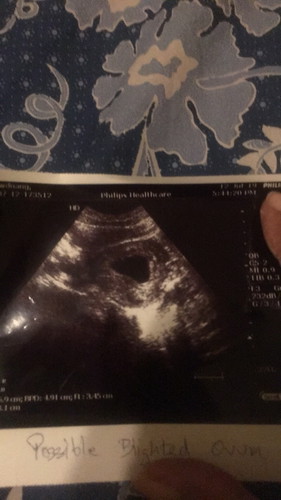

สวัสดีค่ะทุกคน นีมีเรื่องรบกวนสอบถาม เมื่อสัปดาห์ที่แล้ว ครบ8 สัปดาห์ เลยไปฝากท้อง หมอซาวด์หน้าท้อง หมอ ไม่เจอตัวอ่อน หมอเลยสันนิฐานว่าน่าจะท้องลม แต่ ก็นัดมาตรวจอีก คือเมื่อวาน ครบ1อาท

คราวนี้หมอซาวช่องคลอด ไม่เจอค่ะ หมอเลยวินิจฉัยว่า ท้องลม หมอก็แนะนำ ว่า จะรอให้หลุดเองหรือจะไป รพ. เพื้อจัดการ ขูดหมอลูกก็ได้ ตามสะดวกของ คุณแม่ เสียใจค่ะ ท้องแรก เลยอยากสอบถามว่า สัปดาห์ที่แล้ว ถุงมีขนาด1.5 ซม สัปดาห์นี้ถุงมีขนาด 7 ซม ตามภาพที่แนบ เราควรรอ อีกสักอาทิตย์ หรือตามคำหมอแนะนำ คือไป รพ เพื่อเตรียมพร้อม ในครั้งต่อไปดี ค่ะ ทำอะไร ไม่ถูก มันตื้อ มันงง ขอบคุณค่ะ